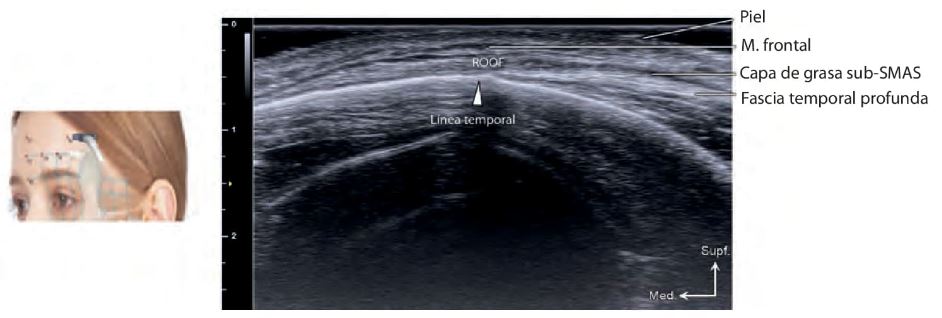

La cara y el cuello están compuestos por cinco capas anatómicas: piel, tejido subcutáneo, SMAS, ligamentos de retención y fascia profunda. La ecografía permite visualizar estas capas en tiempo real, facilitando la identificación de estructuras críticas como vasos, nervios y compartimentos grasos.

El tejido adiposo facial está dividido en compartimentos superficiales y profundos, cada uno con características únicas de vascularización, textura y soporte conectivo. La ecografía permite evaluar el estado de estos compartimentos, lo que es clave para:

La visualización ecográfica de estos compartimentos permite adaptar las técnicas a las necesidades anatómicas individuales del paciente.